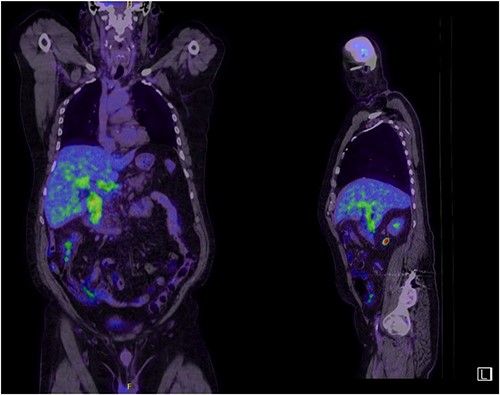

A man in his 70s presented to the emergency department with painless obstructive jaundice with dark urine and pale stools. The patient denied having any fever, nausea, vomiting, or weight loss. Liver function test progressively worsened during the admission peaking at a bilirubin of 287 umol/L (normal 2–20), alkaline phosphatase 694 U/L (normal 30–110), and alanine aminotransferase 160 U/L (normal < 40). Initial assessment on computed tomography and ultrasound raised concerns for primary pancreatic head neoplasm or cholangiocarcinoma (Fig. 1). He subsequently underwent magnetic resonance cholangiopancreatography (MRCP), which showed involvement of the entire common bile duct with no definite stricture or dilatation and no discrete pancreatic head mass (Fig. 2). Positron emission tomography showed abnormal uptake in the intrahepatic and extrahepatic bile ducts, focal uptake in the tail of the pancreas, and lymph nodes in the porta hepatis, retroperitoneum, and right iliac fossa (Fig. 3). Tumour markers revealed a carbohydrate antigen 19-9 (CA19-9) of 3286 kU/L (normal < 34).

CT scan showing thickening and enhancement of the entire extrahepatic common bile duct with intrahepatic duct dilatation.